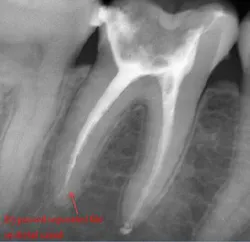

Step 3: Obturate

Canals are carefully dried with paper points. Insert the gutta-percha with AH sealer in the canal to working length, and take it back out. Add additional sealer to the gutta-percha, and then in a gentle pumping motion insert gutta-percha back to working length. Sear off access with a thermal pen and apply gentle pressure with a condenser.

Using a pumping motion and adding additional sealer ensures that voids within the canals get filled. This generates the “puff” effect with small amount of sealer being extruded from the apex of canals. It also helps ensure accessory canals are not left unfilled.